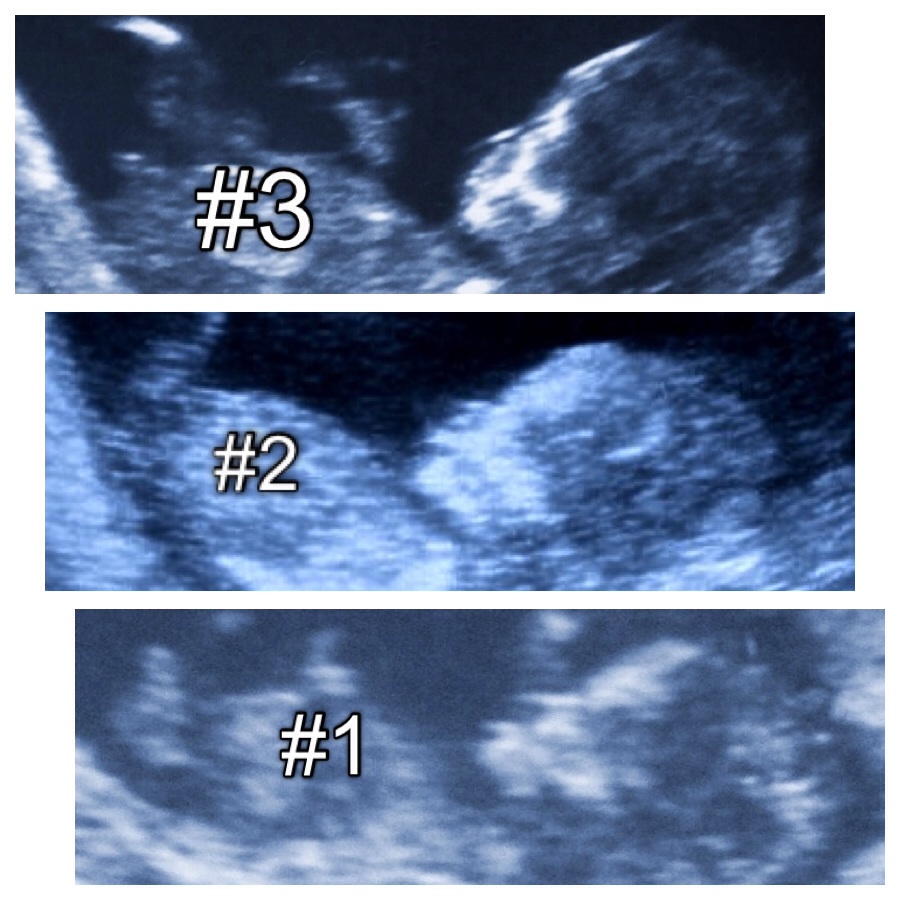

Bottom photo is of my recent 18+2 scan potty shot

Attachment 14572

Please please let me know your thoughts??